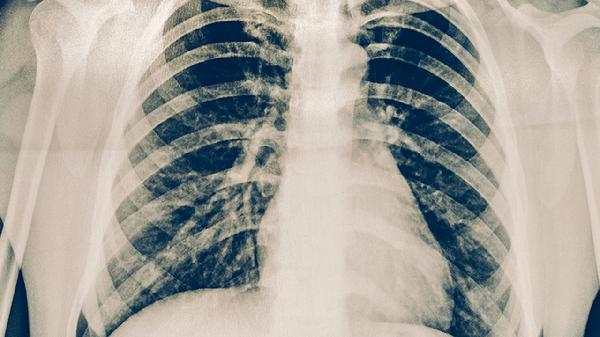

支气管肺炎患者可以遵医嘱使用阿莫西林克拉维酸钾片、盐酸氨溴索口服溶液、布地奈德福莫特罗吸入粉雾剂、阿奇霉素干混悬剂、复方甘草片等药物。支气管肺炎可能与细菌感染、病毒感染、支原体感染等因素有关,通常表现为咳嗽、咳痰、发热等症状。建议及时就医,积极配合医生治疗,在医生的指导下服用合适的药物,并做好饮食调理。